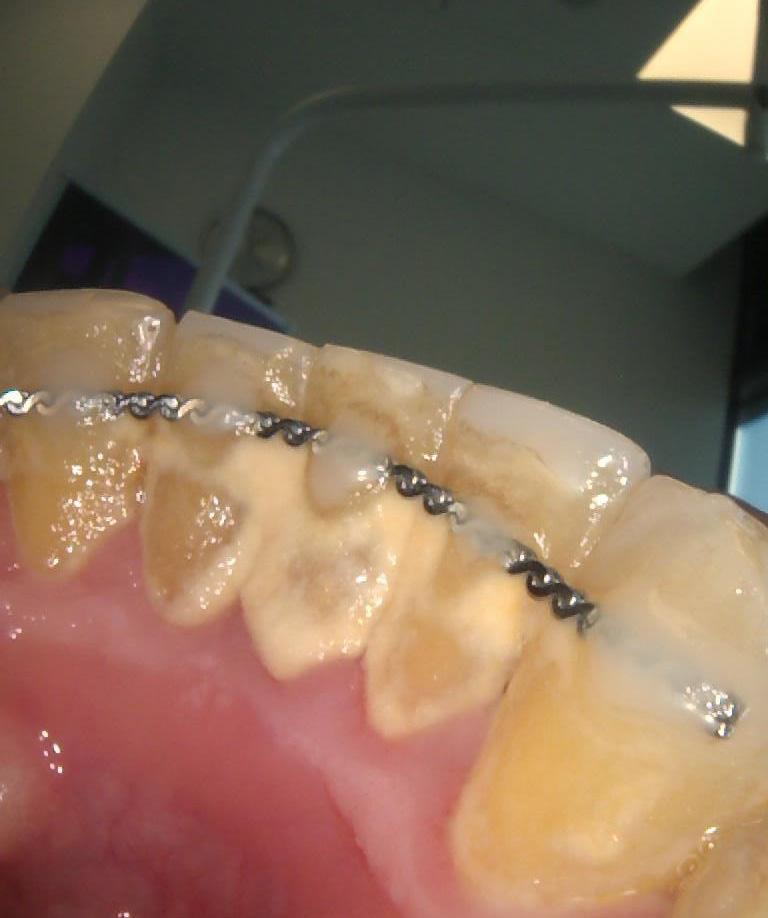

Pacjent po długotrwałym leczeniu chirurgicznym i ortodontycznym w Klinice Platinum został skierowany do lekarza protetyka dr Magdaleny Zawirskiej celem zlikwidowania obecnych trem i diastemy oraz poprawy kształtu zębów.

dr Magdalena zastosowała innowacyjną metodę odbudowy zębów, znaną jako bonding. To bezpieczna i nieinwazyjna technika, która nie wymaga szlifowania zębów. Dzięki wykorzystaniu materiału kompozytowego, został osiągnięty natychmiastowy efekt – od razu już po jednej wizycie.

Teraz Pacjent może pochwalić się pięknym uśmiechem!